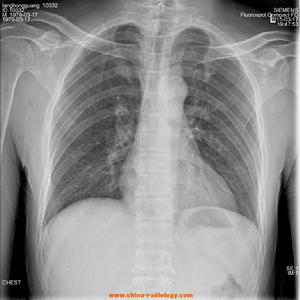

人體X光圖片 軔致輻射:當高速電子流撞擊陽極靶受到制動時,電子在原子核的強電場作用下,速度的量值和方向都發生急劇的變化,一部分動能轉化為光子的能量而輻射出去,這就是軔致輻射。

X射線套用於醫學診斷 ,主要依據X射線的穿透作用、差別吸收、感光作用和螢光作用。由於X射線穿過人體時,受到不同程度的吸收,如骨骼吸收的X射線量比肌肉吸收的量要多,那么通過人體後的X射線量就不一樣,這樣便攜帶了人體各部密度分布的信息,在螢光屏上或攝影膠片上引起的螢光作用或感光作用的強弱就有較大差別,因而在螢光屏上或攝影膠片上(經過顯影、定影)將顯示出不同密度的陰影。根據陰影濃淡的對比,結合臨床表現、化驗結果和病理診斷,即可判斷人體某一部分是否正常。於是,X射線診斷技術便成了世界上最早套用的非刨傷性的內臟檢查技術。